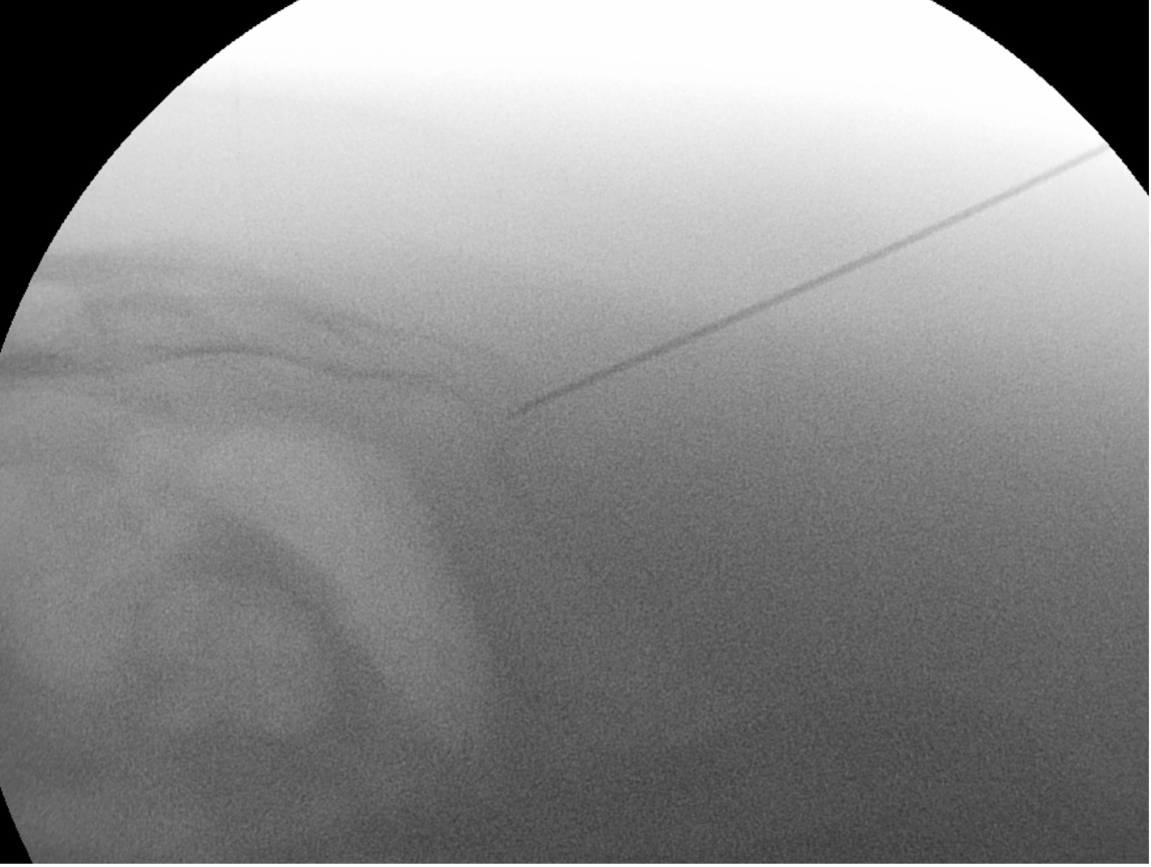

Injections

Injections of local anaesthetic and steroid into the painful sacro-coccygeal or coccyx-coccyx joint are usually helpful for a few months, and allow more effective physiotherapy exercises [10].

The procedure is quite simple and is best performed in the operating room with a brief sedative administered by an anaesthesiologist. Video X-ray is used to guide a needle into the joint(s), and local anaesthetic and steroid are injected (Figure 6).

Fig 6. Injection of the coccyx viewed by a video X-ray system. |